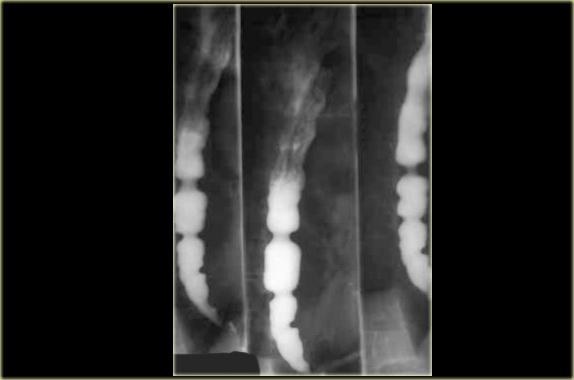

Bên trái: co bóp bậc ba ở lần nuốt đầu tiên (trái).

Co bóp nguyên phát bình thường ở lần nuốt tiếp theo (phải).

Các co bóp bậc ba này là những co bóp không có tính đẩy, thoáng qua và không liên tục, không cố định về vị trí và không kèm theo triệu chứng, thường gặp ở bệnh nhân cao tuổi.

A. Co bóp bậc ba không có tính đẩy ban đầu B. Ba hình ảnh trong quá trình thăm khám cho thấy các ổ đọng thuốc giống túi thừa C. Hình ảnh chụp muộn hơn trong quá trình thăm khám cho thấy các co bóp bậc ba đã biến mất

Đôi khi các co bóp bậc ba thoáng qua có thể giả dạng túi thừa.

Bên trái là hình ảnh của một bệnh nhân có co bóp bậc ba, trong quá trình thăm khám trông giống như túi thừa.